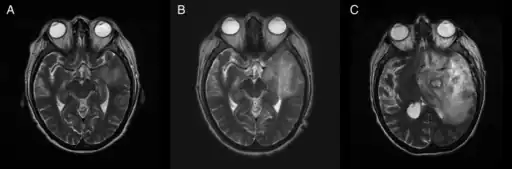

T2-weighted MRI showing liquefied, necrotic brain tissue as a result of GAE caused by an infection of Acanthamoeba, genotype T18